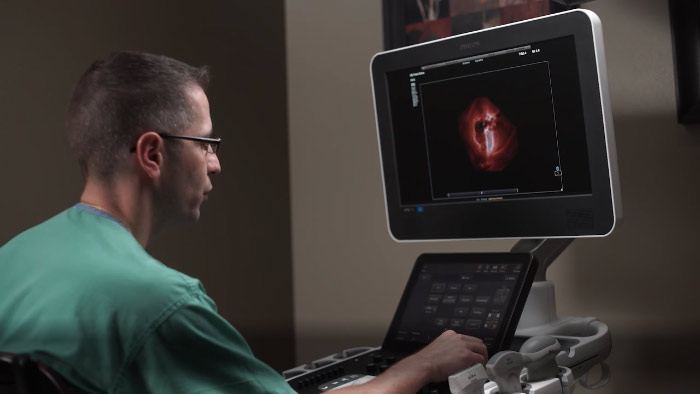

En este vídeo, el Dr. Michael Ruma, de Perinatal Associates, Nuevo México (EE. UU.), explora el uso de la función aBiometry Assist and Tilt de Philips para exploraciones de obstetricia/ginecología.

Philips TrueVue, TouchVue, GlassVue, aReveal

En este vídeo, el Dr. Michael Ruma, de Perinatal Associates, Nuevo México (EE. UU.), explora el uso de TrueVue, TouchVue, GlassVue y aReveal de Philips para exploraciones de obstetricia/ginecología.

Philips eL18-4 with Microflow imaging (MFI)

En este vídeo, el Dr. Michael Ruma, de Perinatal Associates, Nuevo México (EE. UU.), explora el uso del transductor de ultra banda ancha eL18-4 de Philips y MicroFlow Imaging de Philips para exploraciones de obstetricia/ginecología.

Philips MaxVue high definition ultrasound display

En este vídeo, el Dr. Michael Ruma, de Perinatal Associates, Nuevo México (EE. UU.), explora el uso del formato mejorado de pantalla MaxVue de Philips.